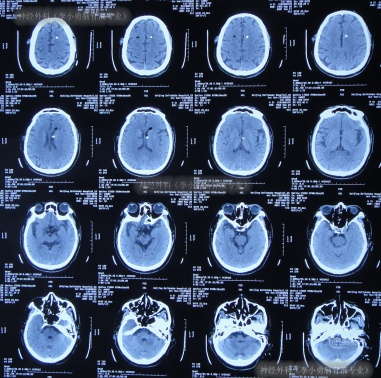

术后次日查头颅CT示脑室有缩小(图-4),意识也有好转。

图-4:2020年12月9日头颅CT